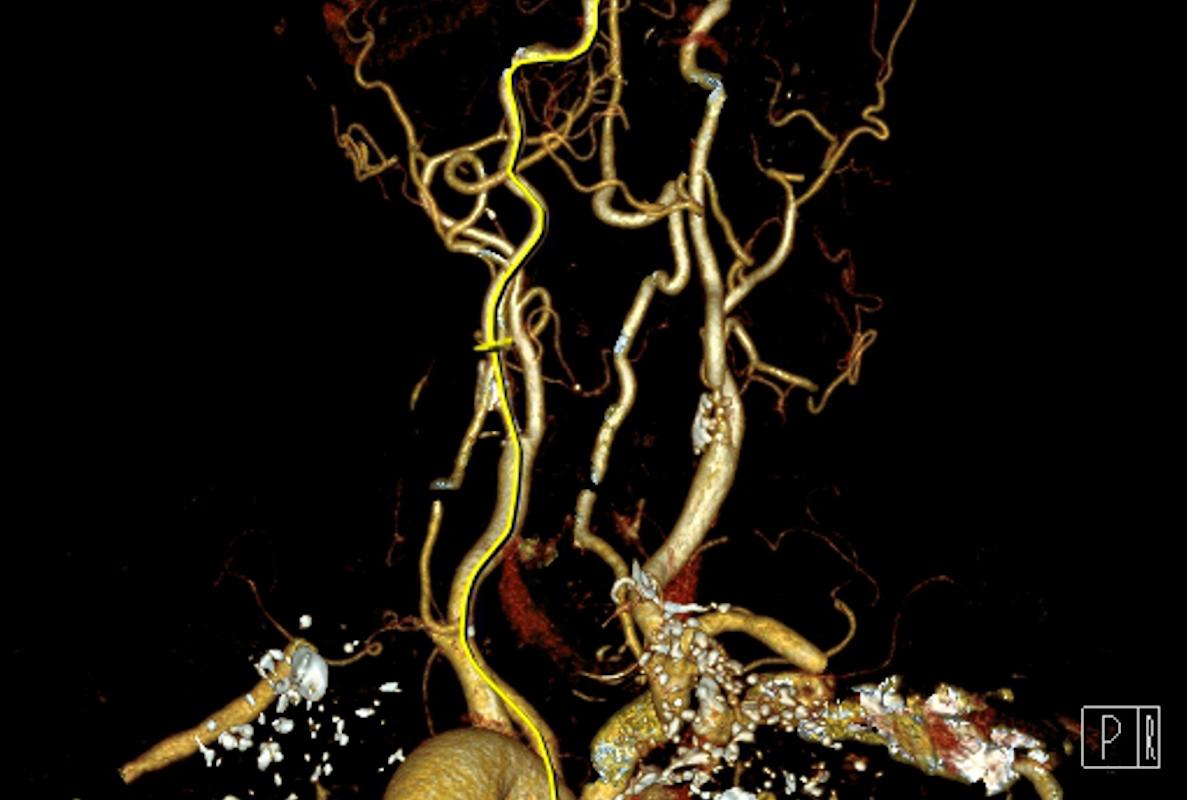

Le traitement actuel des sténoses carotidiennes symptomatiques repose sur des études anciennes (ECST, NASCET) datant de plus de trente ans. Les recommandations basées sur ces essais recommandent l'endartériectomie carotidienne chez les patients souffrant d'une sténose carotidienne symptomatique récente de 70 à 99 % et dans les sous-groupes de patients avec une sténose symptomatique de 50 à 69 %. Depuis, les avancées notables des traitements médicaux remettent en cause ces recommandations.

Ces données proviennent de l’étude ECST-2, un essai multicentrique randomisé mené dans 30 centres spécialisés en Europe et au Canada, incluant 429 patients avec une sténose carotidienne ≥50 %, symptomatique ou asymptomatique, mais à risque faible à intermédiaire d’AVC selon le score CAR recalibré. L’analyse a utilisé une méthodologie innovante (ratio gagnant) intégrant les événements cliniques et radiologiques pour renforcer la puissance statistique avec une taille d'échantillon limitée. Bien que la population soit relativement restreinte et principalement caucasienne, réduisant potentiellement la représentativité générale, ces résultats interrogent directement les recommandations actuelles, suggérant une modification de la pratique clinique vers une approche thérapeutique individualisée fondée sur le risque prédictif d’AVC plutôt que sur le seul degré de sténose.

Selon les auteurs, ces résultats appellent à reconsidérer le recours systématique à la revascularisation carotidienne chez les patients à risque faible ou intermédiaire, privilégiant un traitement médical optimisé rigoureux. De futures études devraient explorer l'intérêt de l'imagerie spécifique (IRM carotidienne avec recherche d'hémorragie intra-plaque) pour affiner davantage l'évaluation individuelle du risque et préciser les sous-groupes qui bénéficieraient réellement d'une revascularisation.